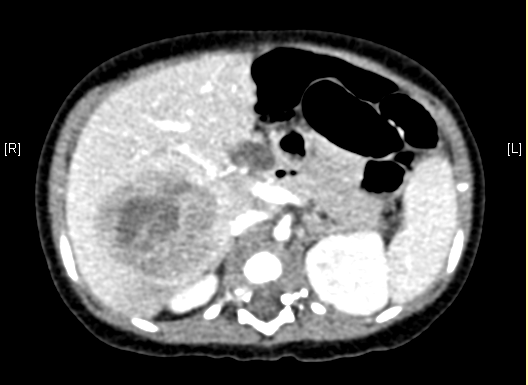

上腹部增强CT:肝右叶巨大占位,肝母细胞瘤可考虑。

术前CT检查:

平衡期